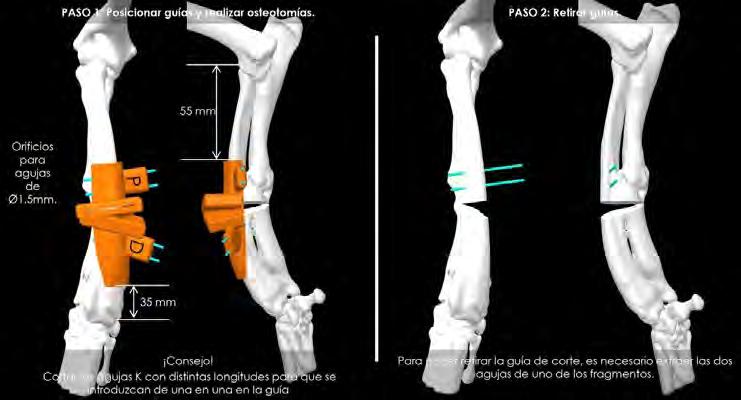

el empleo de guías quirúrgicas específicas. Estos dispositivos permiten reducir el tiempo de cirugía, aumentar la precisión (obteniendo mejores resultados) y disminuir errores en quirófano. Estas guías están diseñadas para encajar perfectamente sobre el hueso, puesto que se ha copiado la geometría de la TC, contando con dos ranuras para introducir la hoja de la sierra y realizar los cortes, con la orientación necesaria para obtener la corrección prevista (Fig. 3A).6,7 En este caso, se planificó la corrección para modificar la deformidad angular que sufrían cúbito y radio, adaptando lo más posible la anatomía de estos huesos a su conformación espacial deseable (en sus tres planos anatómicos: sagital, frontal y transverso), que en ocasiones es la del miembro contralateral, si en este no hay deformidad o es mínima.

Tras exponer el radio, el primer paso consistió en posicionar la guía de corte en la zona cráneo/medial del área media/distal de este hueso (según lo planificado), fijando temporalmente su posición con la ayuda de 4 agujas introducidas a través de los orificios proximales y distales de la guía. Una vez fijada, se realizaron los cortes con una sierra oscilante recta a través de las dos ranuras del dispositivo (Fig. 3B). A continuación, en un segundo paso, se retiró la guía de corte y se sustituyó por la de alineación, empleando el mismo sistema de fijación con agujas para conseguir la reducción de los fragmentos, según la planificación prevista. Esta segunda guía está diseñada para poder mantener en la posición adecuada los fragmentos mientras se estabilizan con la placa principal (Fig. 4A).

Figura 3. (A) Reproducción en 3D de la aplicación de la guía quirúrgica que permitirá realizar los cortes adecuados sobre el cúbito y radio (ostectomía) posibilitando así la mejor alineación de estos huesos. (B). Imagen de la colocación de la guía quirúrgica durante la intervención.

Figura 5. Proyecciones radiográficas craneocaudal y mediolateral posquirúrgicas. Las radiografías muestran el resultado tras la cirugía.